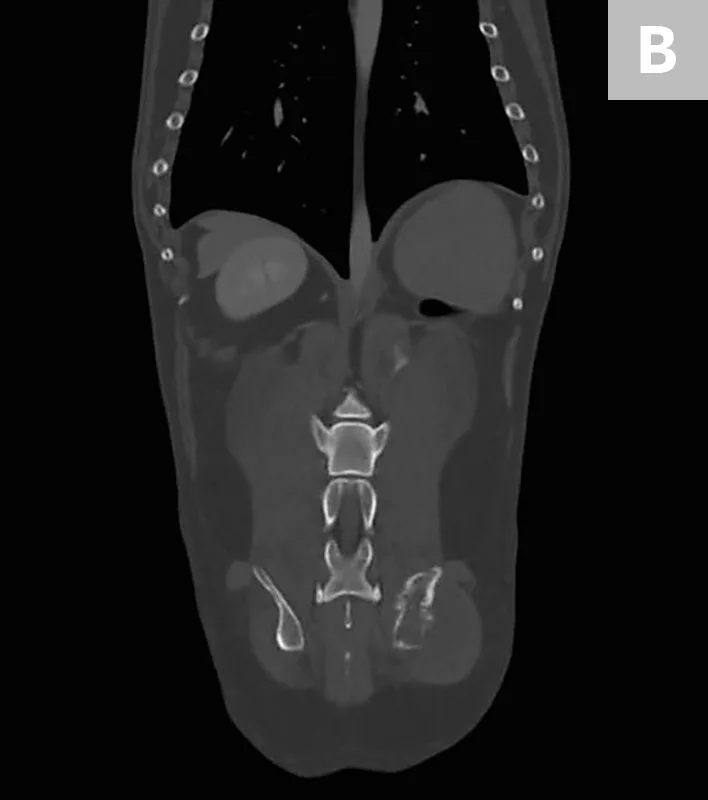

FIGURE 1

Axial (A) and coronal (B) CT images from the patient. An aggressive bone lesion arising from the left ilium, with extension to the surrounding soft tissues, can be seen.

Diagnosis

CBC, serum chemistry profile, and urinalysis results were unremarkable. Three-view thoracic radiographs showed no evidence of gross metastatic disease. A CT scan of the chest, abdomen, and pelvis showed an aggressive bone lesion of the left ilium, compatible with osteosarcoma, with tumor extension to the surrounding soft tissue (Figure 1). A full-body bone scan was performed. Static images were obtained 2 hours after intravenous injection of Tc99m-MDP. There was marked uptake in the area of the primary tumor (ie, the left ilium). There was also a possible metastatic lesion in the left costal cartilages; however, careful review of the CT scan showed that the increased uptake of radiopharmaceutical at that site was most likely consistent with old trauma rather than metastatic disease (Figure 2).